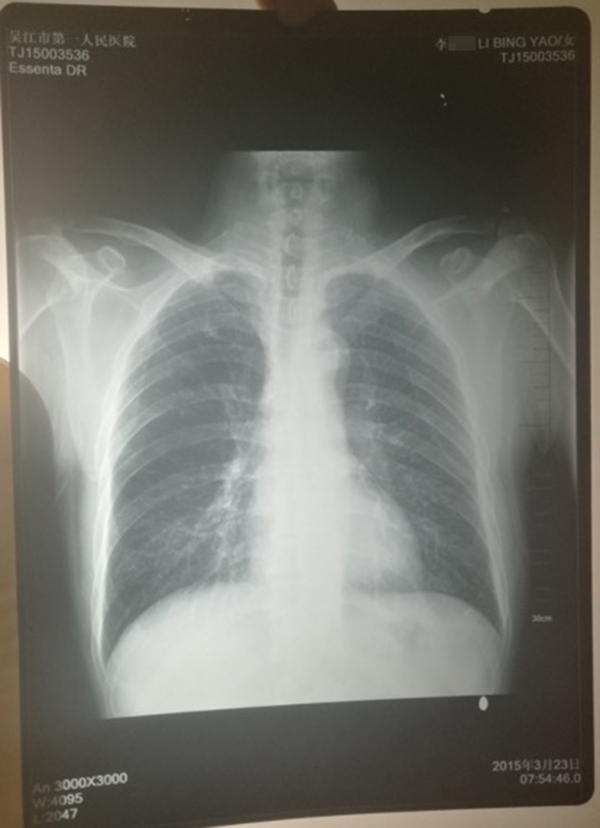

醫(yī)院提供的計建宏的“真實胸片”,寫有姓名“李某某”。 受訪人供圖

計云強稱,吳江區(qū)第一人民醫(yī)院曾提供一份印有“李某某”姓名的胸片,并稱該胸片才是計建宏的“真實影像結果”。

對于“李某某”姓名的胸片,上述吳姓主任稱,經(jīng)過醫(yī)院核查,兩份胸片的結果都是“正常”的,“如果結果是不一樣的話,那么問題就大了,但是因為是一樣的結果,所以不能認為是‘漏診’或‘誤診’。”